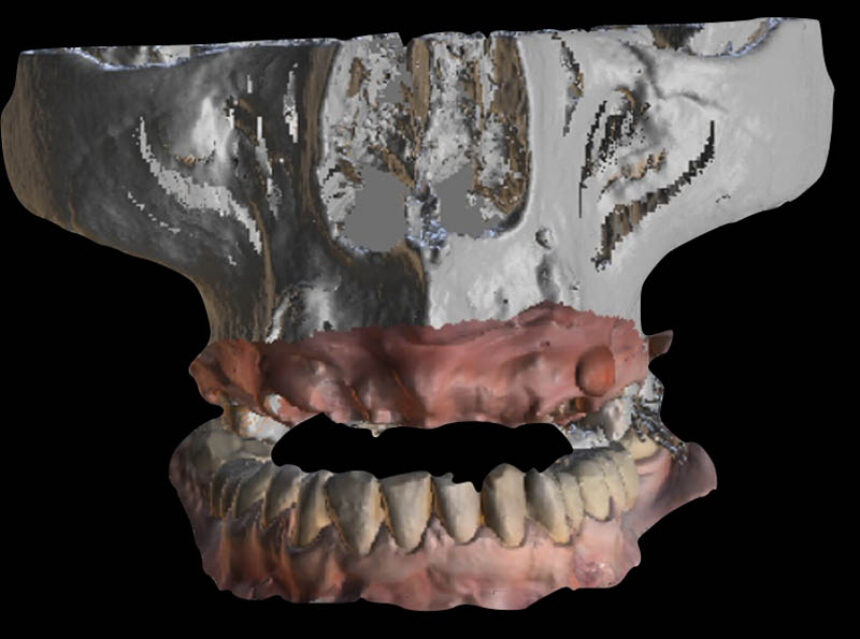

Today one of the biggest problems in Implant dentistry is the increasing prevalence of cases affected by peri-implantitis. The literature shows that up to 20% of our clinical cases might be affected by this disease and any efforts to treat it and achieve long term stability have failed till now. The purpose of this course is to clarify the related risk factors in all aspects of treatment, from case selection to implant placement to prosthesis delivery, and provide simple protocols of treatment that can ensure ideal conditions for long term stable results.

The modern day clinician is constantly receiving information regarding digital dentistry and computer-guided implantology. Inevitably it leads to information overload leaving the dentist overwhelmed about the whys and hows and whether these new technologies can really help him in his daily clinical practice. Together we will discuss and analyze the details and steps behind each digital tool and how we will start incorporating them correctly into our clinic, always using them guided by the biological factors that rule implantology.